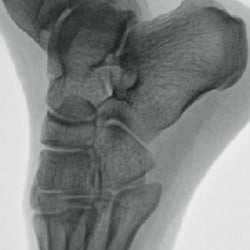

Metal correction

Minimizing halation for clear visualization in orthopedic procedures with bolts and implants.

No metal correction